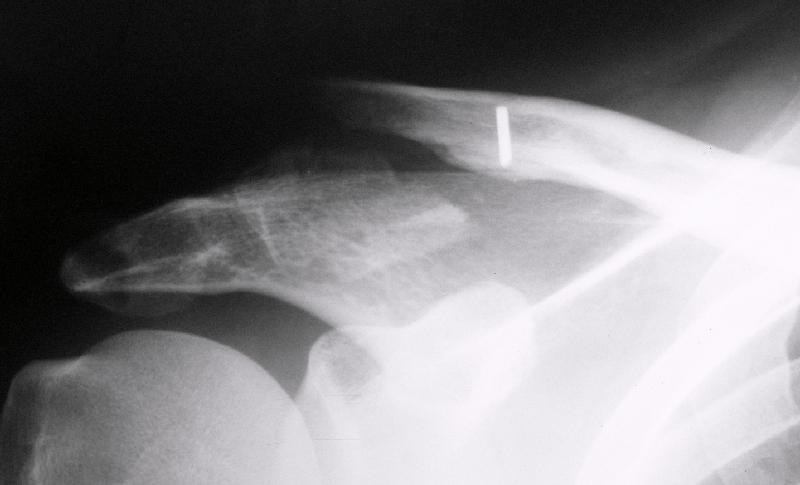

Первично правильно сопоставленный перелом (небольшой разрез, спицы) привел бы к тому, что костный фрагмент, отрванный ключично-клювовидной связкой, лег аккурат под своим ложем и тесно к нему... то бишь в итоге сросся бы без проблем... (кстати на вашем снимке костный фрагмент "оскольчатого перелома" консолидирован... то есть даже достигнутая вами несостоятельная фиксация привела к приростанию авульзионно оторванного

фрагмента)

То, что было представлено на вашем снимке - ... - создается впечатление что никакой консолидации в области перелома (основного) достигнуто не было...

Причина? Аппарат? Может быть центральный отломок был смещен кпереди или кзади?

Я бы назвал данный перелом как перелом с костной авульзией ключично-клювовидной связи... Потому как данный фрагмент лежит вне основной зоны перелома...